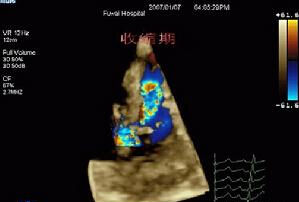

左室中部狹窄合併重度肺動脈高壓1.實驗室檢查:自身抗體、肝功能與肝炎病毒標誌物、HIV抗體、甲狀腺功能檢查、血氣分析、凝血酶原時間與活動度、BNP或NT-proBNP.2.心電圖提示右室超負荷、肥厚和右房擴張。

4.超聲心動圖:用於估測肺動脈壓力,排除其他病因,如先心病、瓣膜病等,還可評價右心功能、判斷預後。